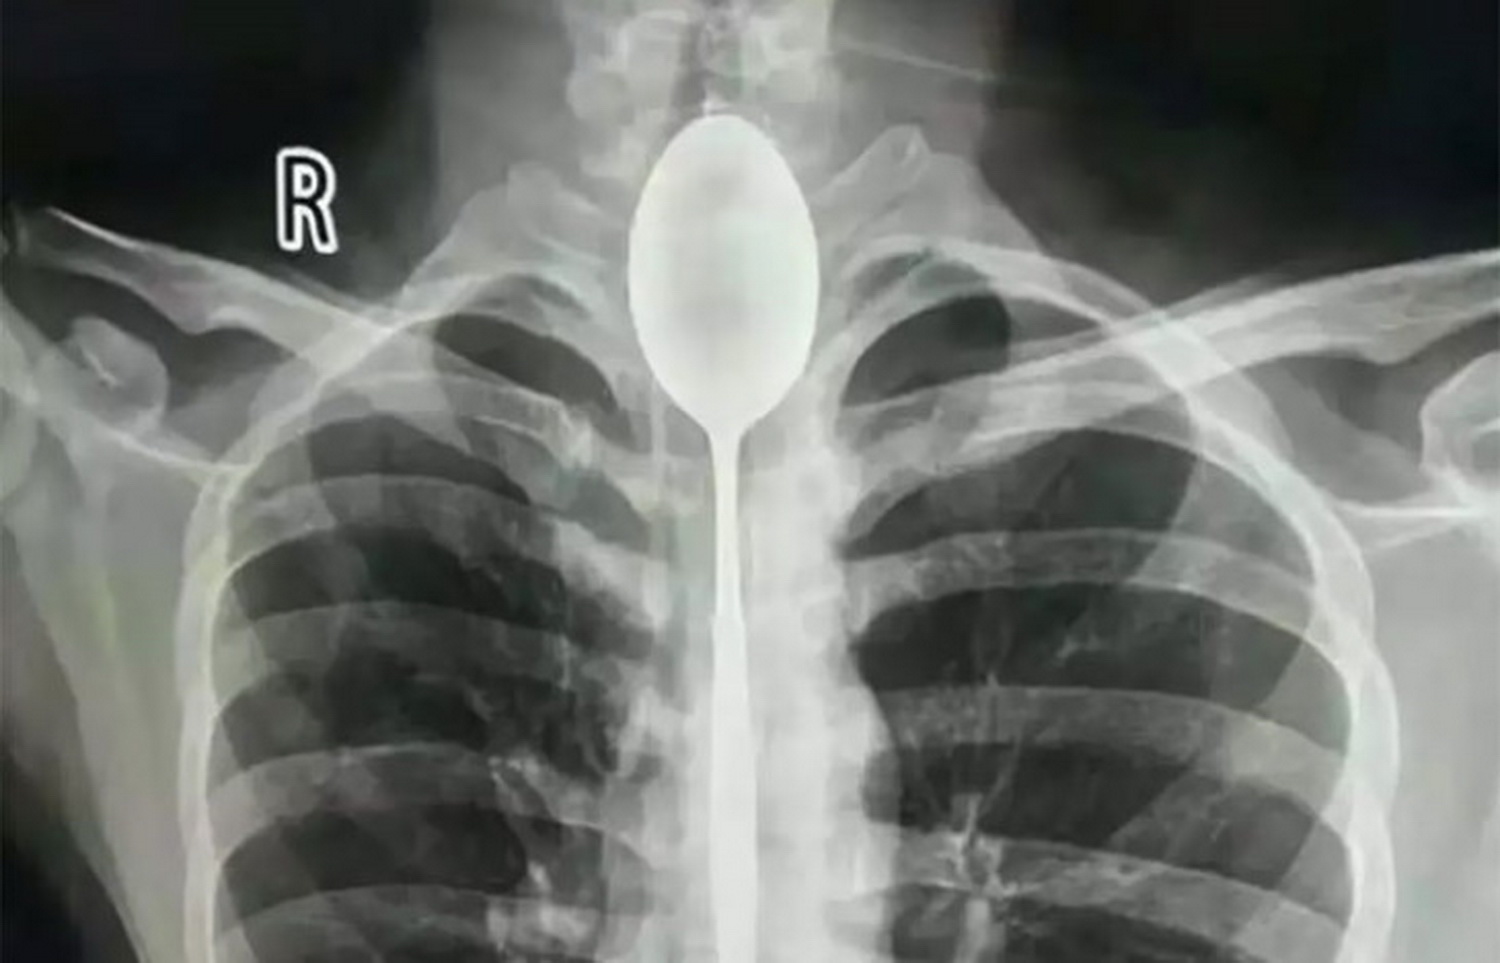

А у этого человека ложка застряла в пищеводе. По его словам, она причиняла ему некоторые неудобства